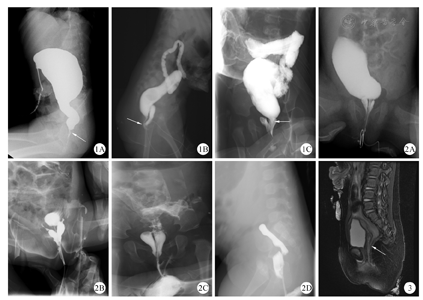

术前行阴道超声检查3例,2例有阳性发现,分别为阴道后缘低回声条和阴道后壁与直肠界限不清。行自造瘘口造影3例可见瘘管显影(图1);行自会阴部逆行造影3例可见双阴道和直肠瘘管显影(图2)。行盆腔MRI检查1例可清晰、全程显示瘘管位置和走行(图3)。本研究已通过我院伦理委员会审批([2021]-E-019-R),所有患儿家长均知情并签字同意手术治疗。

国内外都曾长期存在对CRVF的误诊[2,7]。Oh等[1]报道17例由外院转诊的CRVF,仅7例诊断准确,另有泄殖腔畸形6例、直肠前庭瘘3例和肛门闭锁无瘘1例。Peña等[8]报道42例以"CRVF"转诊的病例也均系误诊,其中12例为直肠前庭瘘,30例为泄殖腔畸形。因此,应从解剖角度严格界定CRVF的诊断:常见为女童外阴,正常肛穴处无肛门开口,小阴唇间可见正常尿道外口和阴道口,直肠开口在阴道后壁、处女膜近端,舟状窝处无瘘口[8]。在临床工作中,通过小儿外科医师简单的会阴部查体,可较大程度上减少误诊。通过查阅相关文献,总结本组病例经验,我们认为可以通过以下方法提高CRVF诊断准确率:①推荐进行完善的术前影像学检查。消化道造影是最重要的诊断性检查[9,10]。本组有3例经造瘘口远端造影,可见直肠与阴道相通;3例合并双阴道畸形患儿经会阴窦道逆行造影,可见类似"蝴蝶样"双阴道显影。有经验的超声医生还可通过观察阴道后壁与直肠的关系判断是否存在瘘管[11]。如术前会阴部不能明确观察到直肠瘘口,必须行盆腔MRI检查,用以判断瘘管位置、走行[12,13]。同时了解子宫卵巢和盆底肌发育情况。本研究中1例行盆腔MRI检查患儿,矢状位T2WI压脂像可清晰显示瘘管位置及走行。②重视麻醉下对会阴部的再检查。常规查体可能因患儿不能配合,造成会阴部暴露困难,故可在患儿麻醉后,术前再检查。患儿取截石位:提起双侧大阴唇,观察尿道、阴道、直肠瘘口位置及相互关系。本组绝大部分误诊病例经此环节可明确诊断。与之相对,本组有1例术前在外院以"直肠前庭瘘"拟行Peña术,麻醉后未再次检查会阴,仍以无肛前庭瘘标准手术,导致对直肠位置估计不准,手术失败。